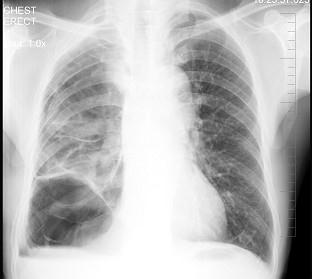

男性患者,62岁,常感胸闷、气逼,X线检查如图,最可能的诊断是 ( )A.右侧肺大疱B.右侧气胸C.右侧肺脓肿D.右侧胸膜肥厚E.气胸

问题 男性患者,62岁,常感胸闷、气逼,X线检查如图,最可能的诊断是 ( )

选项 A.右侧肺大疱 B.右侧气胸 C.右侧肺脓肿 D.右侧胸膜肥厚 E.气胸

答案 A